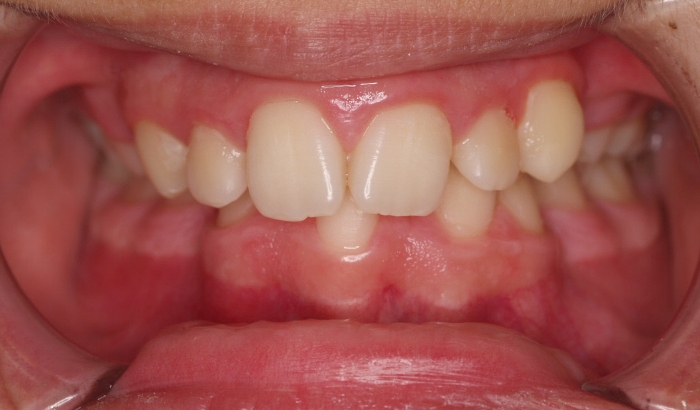

Fotos después de tratamiento:

El paciente ha sido tratado con brackets DAMON Q de acero. La duración del tratamiento ha sido de 2 años.

Después de finalizar el tratamiento fijo, lleva férulas de contención arriba y abajo. Además de una contención fija de 3 a3 inferior.